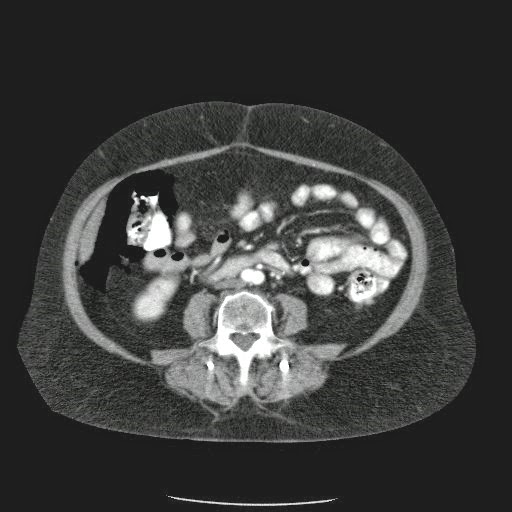

Paciente con antecedente de ALIF (Fusión lumbar intersomática anterior) 360 grados L5-S1 hace siete meses, quién presenta herida de abordaje anterior con dehiscencia de sutura, con cierre por segunda intención, quien consulta por cuadro clínico de dos días de secreción purulenta en herida quirúrgica, niega fiebre, niega otras sintomatología, refiere episodios previos similares.

Paciente en POP de ALIF L5-S1 quien presento dehiscencia de la herida abdominal con ISO superficial ya tratada, sin embargo persiste con dehiscencia y desde ayer con supuración asociado a fiebre subjetiva. Se realiza eco abdominal con colección en pared sugestiva de absceso, elevación de RFA por lo cual se considera se debe hospitalizar para manejo antibiótico, drenaje de la colección, manejo médico y vigilancia neurológica.

- ¿Hallazgos Escanografia?

2. Hay una colección de la pared abdominal en el flanco derecho, que realza en la periferia con el contraste, e intraabdominal tiene aire pero no me parece colección intraabdominal porque la grasa no está alterada.